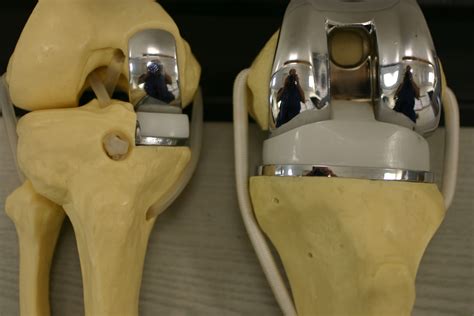

Here is an example of knee replacement images that highlight the benefits of the procedure:

Knee Replacement Benefits

📸 Note: The images above are for illustrative purposes only. Always consult with a healthcare provider for personalized information.